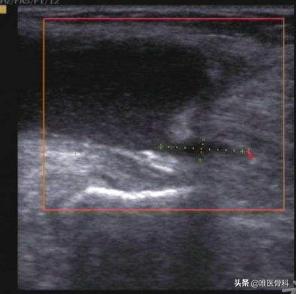

超声在腘窝囊肿的诊断中运用越来越多,其优点为动态观察、费用便宜以及没有辐射。相较于X线而言,超声的优势比较明显,不仅能显示囊肿的位置、大小、形态及内部回声,还能清楚显示囊肿与关节腔及周围组织的关系。